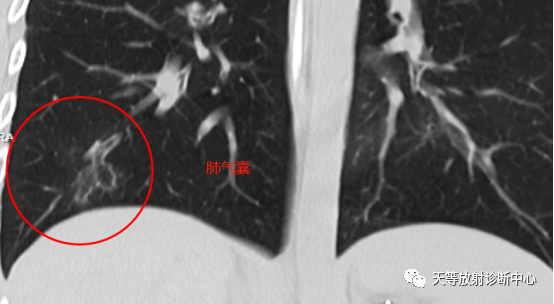

影像学表现:整体观察肺内多发病灶,散在分布,病灶的主要形态为:多发大小不等肺气囊、多发结节共同存在。

1、肺气囊大小不等,张力较大,圆形膨胀感强,周围可见大小不等结节影;